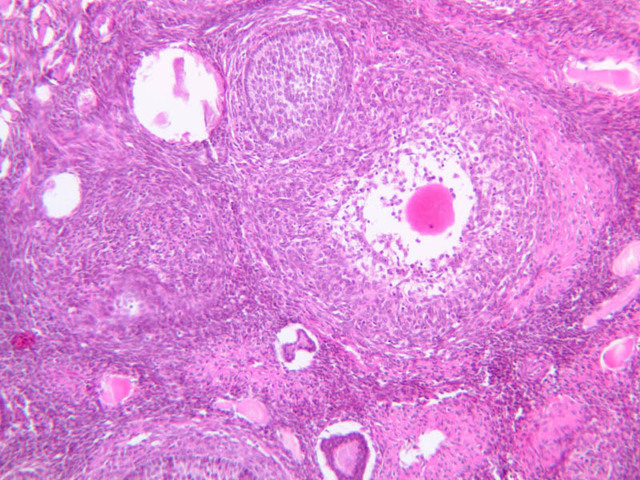

Corpus Luteum

After rupture of the Graafian follicle, the walls collapse and become folded. Thus, strands of tissue from the theca interna penetrate, to some extent, the mass of granulosa cells. Bleeding from the theca interna may form a blood clot in the antrum. The majority of the cells of the corpus luteum are derived from the granulosa cells. Both the granulosa cells and the cells of the theca interna enlarge and accumulate lipid, thus becoming lutein cells. There are two types of lutein cells - granulosa lutein cells that have a large, vesicular nucleus and vacuolate cytoplasm, and theca lutein cells that are distinguished by smaller darker nuclei. Corpus Luteum (slide B-54, human ovary, H&E [1x-labeled, 2.5x, 10x, 20x, 40x-labeled] [1x-labeled, 1x, 2.5x] [1x, 1x, 1x] 1x, 2.5x, 10x]; B-95, H&E [2.5x])